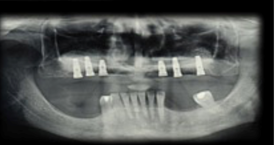

Al presente taller le correspondió evaluar la zona posterior maxilar. El maxilar posterior tiene naturalmente baja altura del proceso alveolar, anatómicamente limitada por el seno maxilar. Las raíces de los molares están muy relacionadas con el piso del seno maxilar. En el centro de la cresta alveolar, se encuentra la región de trifurcación radicular, sitio ideal desde punto de vista protético para la instalación del implante, y donde se encuentra la menor altura de hueso del piso del seno. Lo mencionado hace, que la instalación de implantes de dimensiones estándar después de la pérdida de dientes en ésta región, sea limitada. Los procesos de resorción resultantes de dicha pérdida, común a todas las regiones del proceso alveolar pueden agravar esta situación. La neumatización del seno maxilar, debido al aumento de la actividad osteoclástica a lo largo de la membrana sinusal y la ausencia de la ”barrera” dentaria a los cambios de presiones aéreas sinusales puede afectar la morfología de este sitio. Estas condiciones determinan un desafío anatómico para el tratamiento del maxilar edéntulo posterior utilizando implantes dentales. Las técnicas de reconstrucción de los defectos del reborde alveolar residual con procedimientos de injerto de hueso autógeno tienen resultados predecibles, que se describen en la literatura. Una explicación de sus buenos resultados es el hecho de no tener reacciones inmunes que puedan interferir con el proceso de remodelación y desarrollo del tejido. Tienen intrínsecamente a los osteoblastos y los factores de crecimiento responsables de los cambios celulares que se producen después de la implantación y que culminan en la remodelación y la formación de hueso en ese sitio1. Su desventaja, es la necesidad de un área quirúrgica adicional donante que puede ser de ubicación intraoral, en los casos en que la necesidad de reconstrucción sea pequeña, o extraoral en los casos de medianas o grandes reconstrucciones. En la década de 1980, se han descrito técnicas de injerto de hueso en el seno maxilar con el fin de resolver el problema de la falta de hueso y permitir la colocación del implante. Una de las técnicas descriptas es la cirugía para levantar el suelo del seno maxilar, conocido por su nombre en inglés - Sinus Lift2,3.

Diversas alternativas a la técnica y diferentes tipos de injertos y biomateriales de diferentes naturaleza se han propuesto como una alternativa al uso de hueso autógeno para llenar la cavidad resultante de la elevación del piso del seno. El suministro limitado del hueso autógeno en relación con el volumen necesario para la elevación de seno, así como la facilidad en su uso y técnica con un muy buen rendimiento clínico, animó a la aplicación de biomateriales. Philip Boyne2 (1983) describe la reconstrucción de fracturas con hueso bovino. Sus estudios eran parte del desarrollo de hueso bovino inorgánico, material con alta similitud al hueso humano. Estudios en animales sugieren que el hueso bovino desproteinizado es reabsorbido y sustituido gradualmente por tejido óseo viable. Es un proceso lento comparándolo con autoinjertos4, lo que permite la conservación de la macroestructura reconstruida durante todo el proceso de sustitución. Dependiendo de la disponibilidad ósea (en altura y ancho) en la zona maxilar posterior las opciones para colocar implantes en el lugar correcto son: